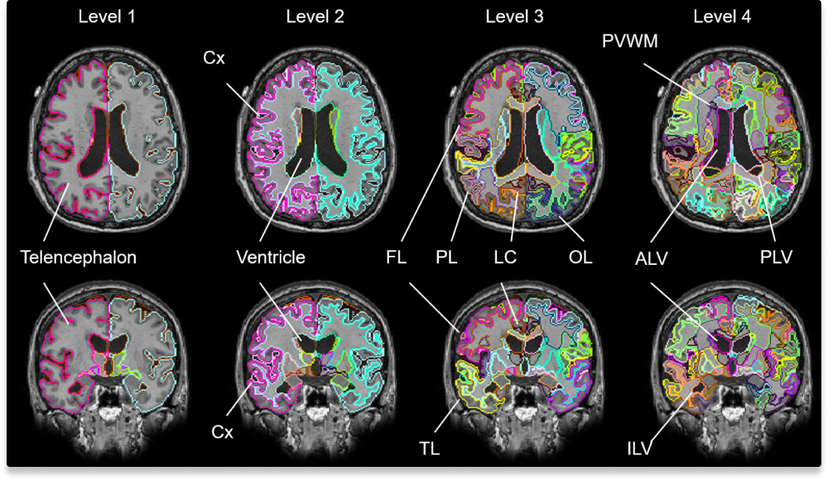

MRICloud技術の活用

クラウドベースの脳MRI画像解析プラットフォーム。世界中の研究者が利用する、信頼性の高い解析環境を提供します。

JHU-Atlas

標準的な脳構造の参照として、高精度な解析を可能にする脳アトラス。